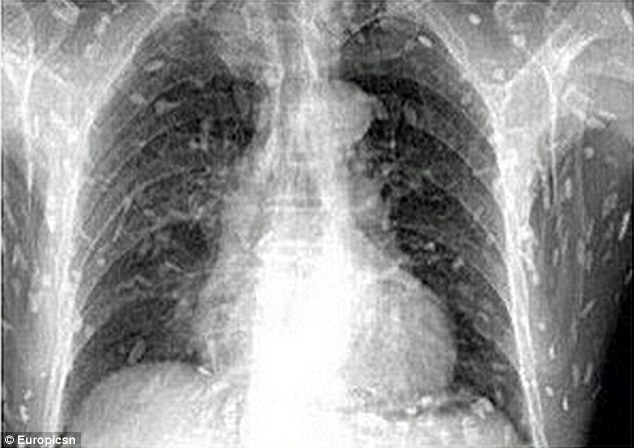

Sau những cơn đau dạ dày và ngứa da, anh đã đến bác sĩ để khám. Thật kinh hoàng khi hình ảnh chụp được cho thấy, toàn bộ cơ thể của anh đã bị nhiễm sán dây sau khi ăn quá nhiều sashimi.

Các bác sĩ tin rằng một số món ăn Nhật chưa nấu chín với nguyên liệu từ thịt sống hoặc cá đã bị nhiễm bẩn là nguyên nhân gây bệnh.

Bệnh nhân đang được điều trị tại Bệnh viện nhân dân Quảng Châu số 8 ở tỉnh Quảng Đông, miền đông Trung Quốc.

Tiến sĩ Yin, Bệnh viện nhân dân Quảng Châu số 8, nói với trang web that'smags.com rằng việc ăn thực phẩm chưa nấu chín có nhiều nguy cơ nhiễm trứng sán dây, gây ra bệnh giun sán. Khi giun trưởng thành và đi vào dòng máu sẽ đe dọa tính mạng của bệnh nhân vì chúng có thể di chuyển đến não hoặc làm tắc mạch máu.